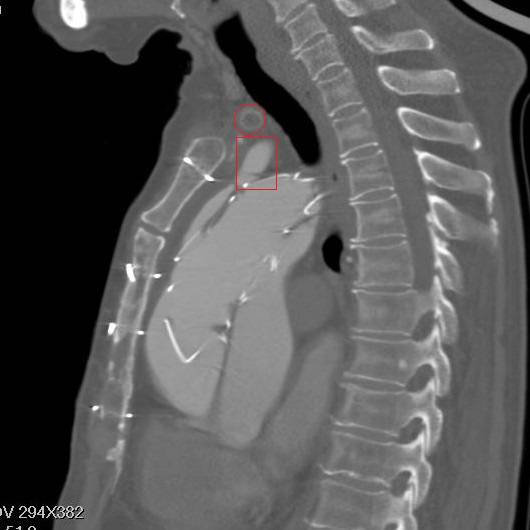

冠状面重建,方框示头臂干看上去完全开口于假腔,左颈总似乎被支架盖住了

矢状面重建,胸骨钢丝很明显,方框示左颈总动脉,支架前端在假腔,后端在真腔。圆框示闭塞的人工血管

方框示左左锁骨下动脉,重度狭窄